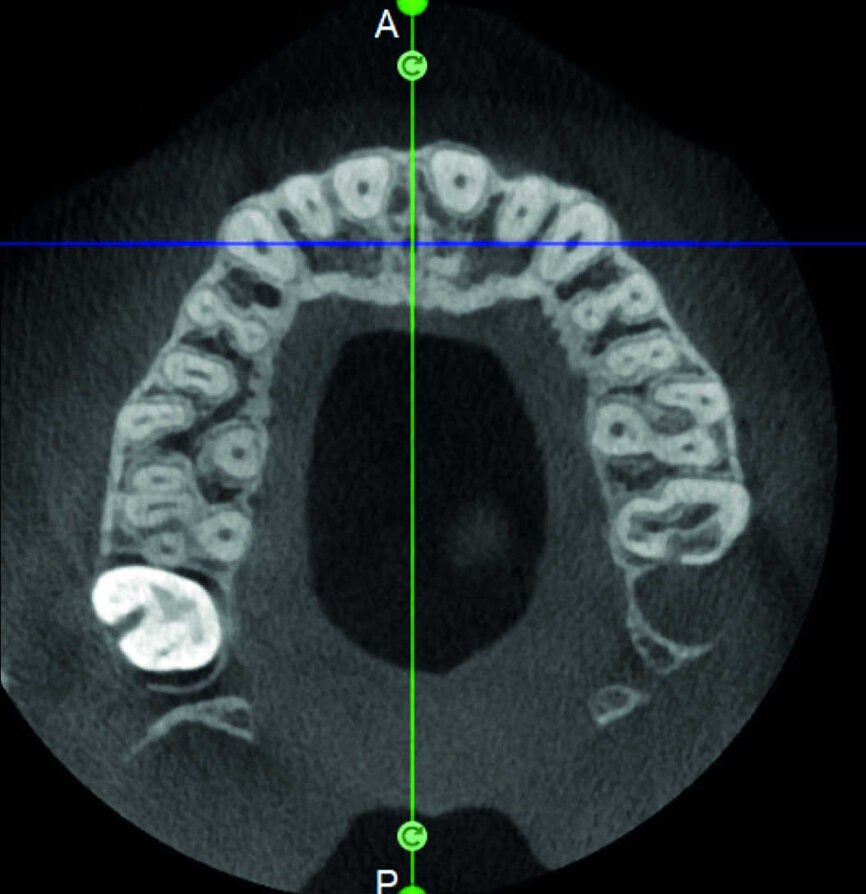

Le cas avec lequel je souhaite commencer mon exposé clinique est un exemple parfait de la difficulté à définir l’origine des symptômes d’un patient, par l’examen d’une simple radiographie intraorale. Non seulement l’examen 2D ne permet pas d’établir avec certitude la présence d’une lésion, mais surtout, il est impossible d’en déterminer la taille, la morphologie et le type. Au contraire, une analyse de l’imagerie 3D offre une image claire de la situation clinique. Chez ce patient, les coupes coronales et sagittales révèlent la présence d’une importante lésion s’étendant de l’apex de la racine mésiale de cette molaire jusqu’à la zone de furcation, tandis que les coupes axiales nous permettent d’analyser précisément l’anatomie endodontique et, en particulier, la forme de la racine mésiale, qui apparaît fusionnée avec la racine palatine. Un panorama complet du cas peut donc guider le processus de décision et orienter le plan de traitement vers une modalité bien précise de traitement (Figs. 1–4).

Indéniablement, l’un des processus pathologiques les plus complexes à traiter est la résorption radiculaire externe invasive, où l’ampleur de la lésion limite les options de traitement. Une évaluation préopératoire de l’emplacement et de l’étendue de la résorption se justifie donc entièrement. Le potentiel de récupération dépend de la planification 3D adéquate de l’intervention, qui ne peut être accomplie qu’après l’examen des clichés CBCT. Il est très important de bien visualiser les coupes de la dent dans les trois plans, et de se concentrer particulièrement sur les coupes axiales, qui s’avèrent stratégiques du point de vue du diagnostic endodontique.

La comparaison des deux dents présentées dans les figures 10 à 22 démontre à quel point il importe d’analyser correctement toutes les coupes de l’examen CBCT. On peut voir que, dans la molaire maxillaire, la lésion commence sur la surface distale de la racine et pénètre dans la cavité pulpaire, mais s’arrête au tiers coronaire de la dent, sans affecter significativement l’intégrité du plancher de la cavité (Figs. 10–15). Les images cliniques illustrent les phases du traitement chirurgical, depuis le débridement de la résorption jusqu’à la restauration au moyen d’un ciment biocéramique (Figs. 16–19). Les clichés radiographiques finaux confirment le bien-fondé du traitement conservateur et endodontique de la dent. La situation est complètement différente pour la molaire mandibulaire, pour laquelle l’évaluation de l’examen CBCT révèle clairement l’étendue de la résorption, qui envahit le plancher de la cavité pulpaire jusqu’à la zone de furcation. Il serait impossible de détecter ce problème par le seul examen de la radiographie préopératoire (Figs. 20–22).